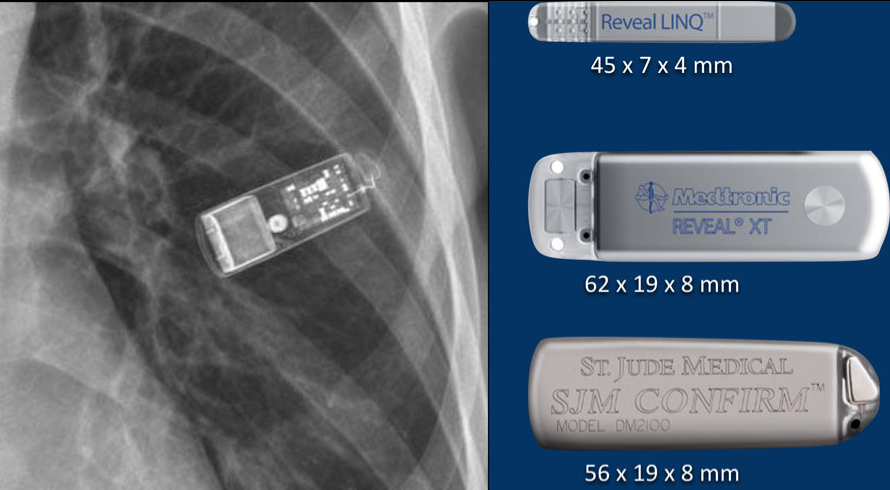

Moniteurs cardiaques implantables sous-cutanés

Reveal